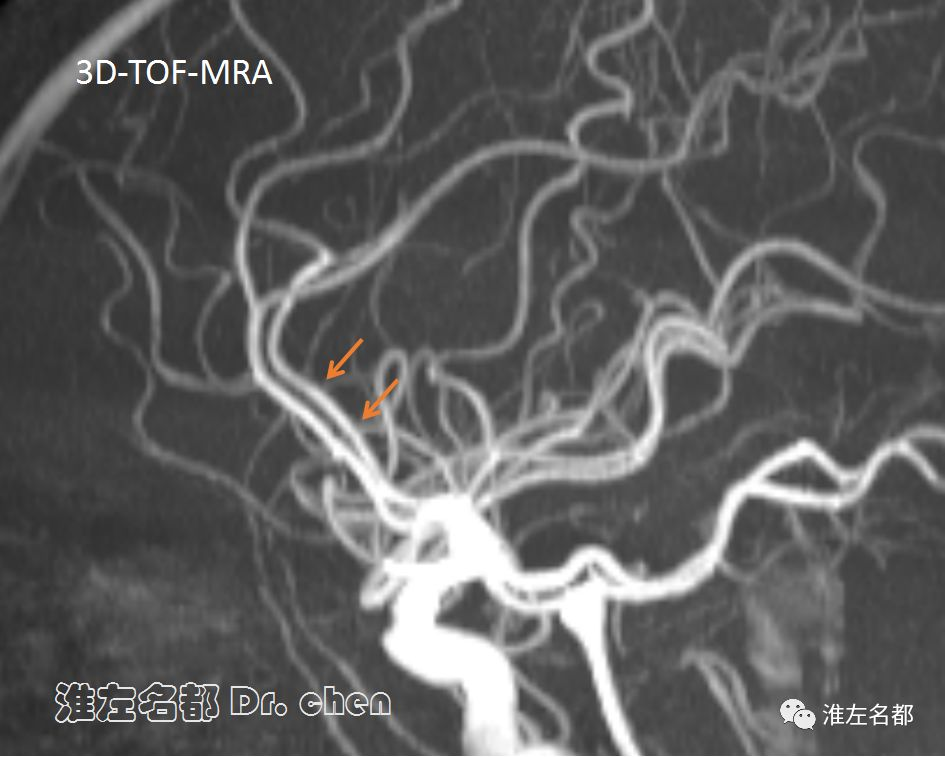

△3D-TOF-MRA和DSA:左侧大脑前动脉A2长节段不规则狭窄(橙箭)